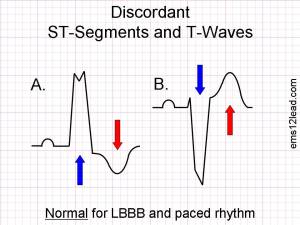

Wie schaut nun ein STEMI -Äquivalent bei LSB aus? Hier kommen die Sgarbossakriterien (4) ins Spiel: ein normaler LSB hat diskordante ST-Segmente und T-Wellen („Rule of appropriate discordance“ -siehe Abbildung 1)

Abb. 1: http://www.ems12lead.com